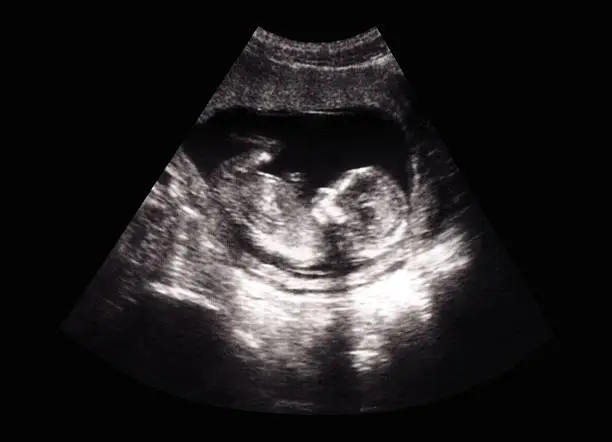

착상혈과 생리는 여성의 생리 주기에서 발생할 수 있는 두 가지 현상입니다. 이 둘은 모두 출혈을 동반하기 때문에 많은 사람들이 혼동할 수 있지만, 사실상 그 원인과 양상에서 명확한 차이를 보입니다. 착상혈은 임신 초기 증상 중 하나로, 배아가 자궁 내막에 착상되면서 발생하는 가벼운 출혈을 의미합니다. 반면 생리는 수정란이 자궁 내막에 착상되지 않아 자궁 내막이 배출되면서 나타나는 출혈입니다. 이를 바탕으로 착상혈과 생리의 차이에 대해 더 깊이 알아보겠습니다.

착상혈은 배아가 자궁 내벽에 자리잡을 때 자궁 내막의 작은 혈관이 손상되며 발생하는 출혈입니다. 이는 임신 초기에 나타날 수 있는 자연스러운 현상이며, 일반적으로 수정 후 6일에서 12일 사이에 발생합니다. 착상혈은 보통 소량의 출혈로, 갈색 또는 분홍빛을 띠는 경우가 많습니다. 반면 생리는 수정되지 않은 난자가 배출되면서 자궁 내막이 떨어져 나가면서 발생하는 더 많은 양의 출혈입니다. 생리는 착상혈에 비해 출혈의 양이 많고 지속 시간이 길며, 붉은색을 띠는 경우가 대부분입니다.